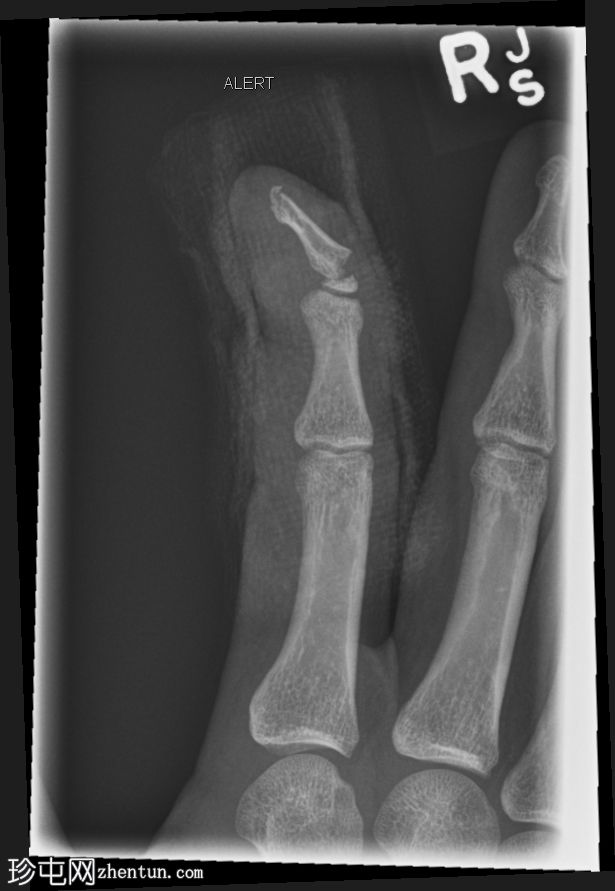

X线片

斜位片

右食指远节指骨基底部横向移位骨折,伴有背侧成角,最符合成人型Seymour骨折。指尖小骨折。

本例为罕见的成人型Seymour骨折,此类骨折通常发生于骨骼未成熟的远节指骨骨骺处。